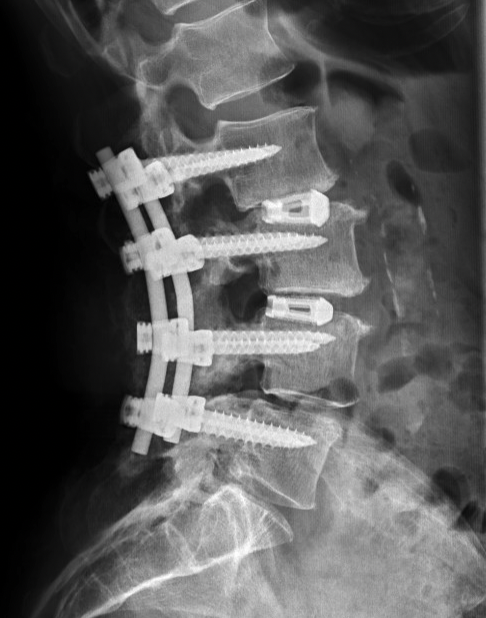

Why Traditional Hardware Can Cause Painful Recoveries

Traditional lumbar fusion surgery often involves screws and rods placed through a posterior incision to stabilize the spine. While this approach can be effective, it often results in a painful recovery, increased surgical time, and a higher risk of postoperative pain. For many patients, the presence of hardware and the additional incisions contribute to a more challenging healing process. CemLIF offers a streamlined alternative, reducing the need for extensive hardware and enhancing the patient experience.